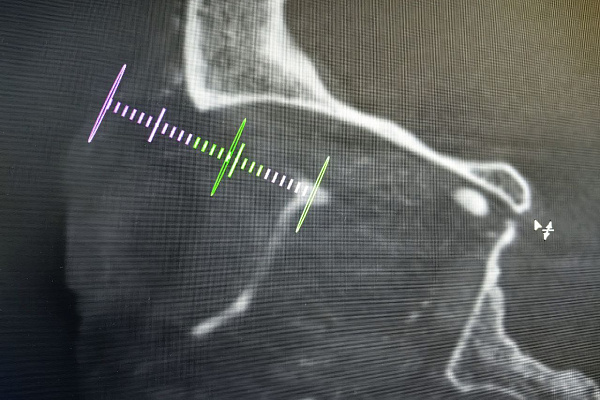

Выбранный путь проходил через верхнюю глазничную щель, рядом с такими важными структурами, как глазной, глазодвигательный блоковый и отводящий нервы. Благодаря возможностям современного ангиографа врач обеспечил себе навигацию в таких сложных условиях и определил оптимальную траекторию. Контрольные снимки после имплантации спиралей и эмболизата подтвердили, что фистула полностью выключена из кровотока.